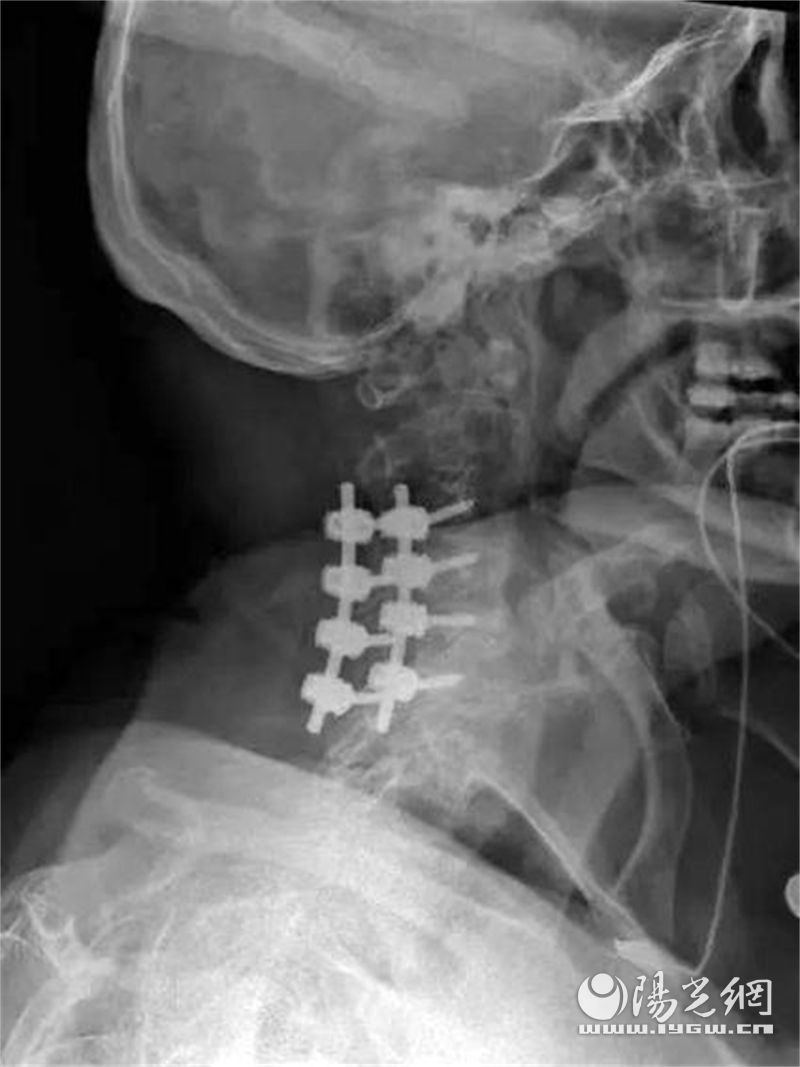

博阿姨有糖尿病病史,身体状况并不理想。经医师、麻醉、护理等团队讨论,深度分析病情,制定了详细的手术方案。手术使用了控制性降压技术,采取后正中切口,通过后正中入路劈开棘上韧带,显露颈3到颈7节段椎板,用磨钻在关节突内侧切开颈3到颈7节段两侧椎板,通过棘突提拉揭开4个节段椎板,完成多节段椎管减压,在颈3到颈7椎体侧块打入螺钉固定,完成后路钉棒固定,随后手术顺利完成。

术前术后对比

术后患者恢复良好。当天转回病房时双腿有了知觉,不到两周,左下肢肌力由1级恢复到3级,右下肢由2级恢复到4级,双腿都能进行轻微的挪动。手术效果可谓立竿见影。两周之后患者转医院康复科继续治疗,科室为其制定了详细的康复计划,目前患者已经可以下地站立,短暂行走。王宁医生说,乐观估计3个月之后便能恢复如初,正常生活。博阿姨女儿激动地说道:“母亲入院时生活都不能自理,这么快已经能自己缓慢的散步,生活品质能有这么大的提升,多亏医院,谢谢医生和护士们,感谢长安区医院!”